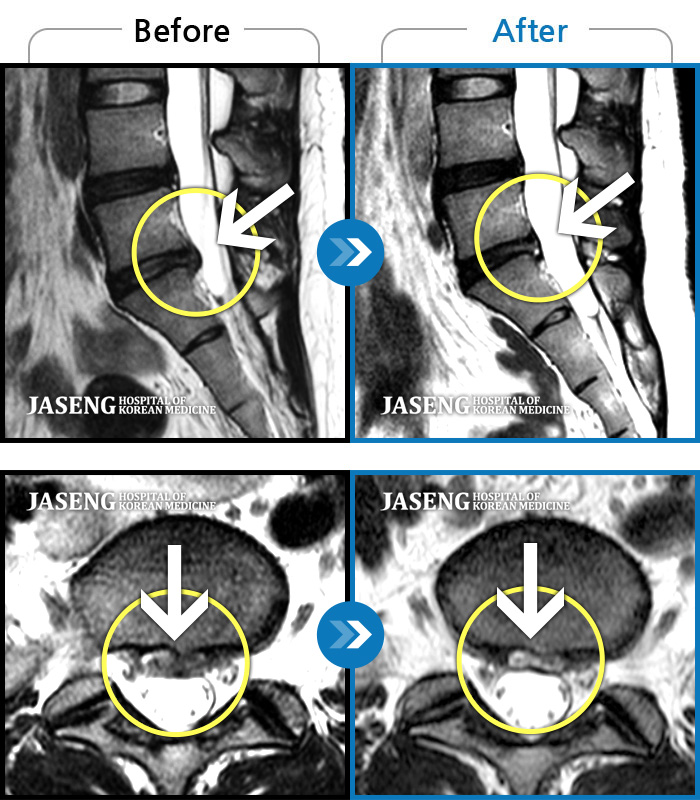

허리디스크

강남 · 이남우 원장

좌측 다리 저림 증상이 너무 심하여 앉거나 서는 것이 안되고 다리를 들어올릴 수 가 없었다.

촬영시기

2023.05.09 ~ 2023.12.12